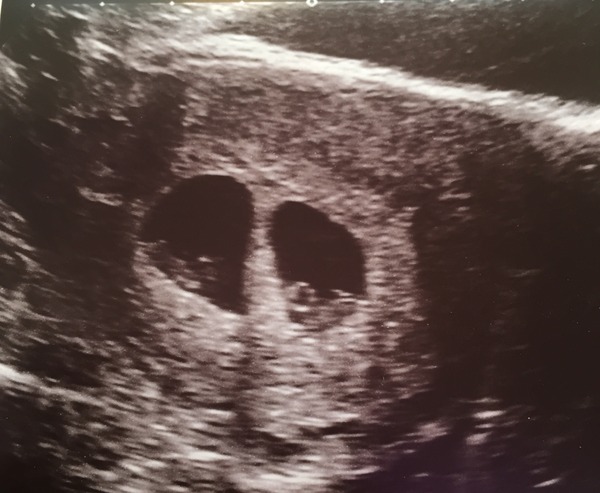

I had spotting Friday afternoon, felt like death so went home and slept, then had more spotting Saturday, the same time I had it last time with my mc. Was booked in for a scan today at 10.20. Guess what? 2 strong heartbeats, we are expecting twins. Both either side of the dates I had for ovulation so I am 6+4 with one and 6+6 with the other!! Will post a pic for you all